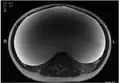

Imaging

-

MRI giant serous cystadenoma of ovary -

MRI giant serous cystadenoma ovary